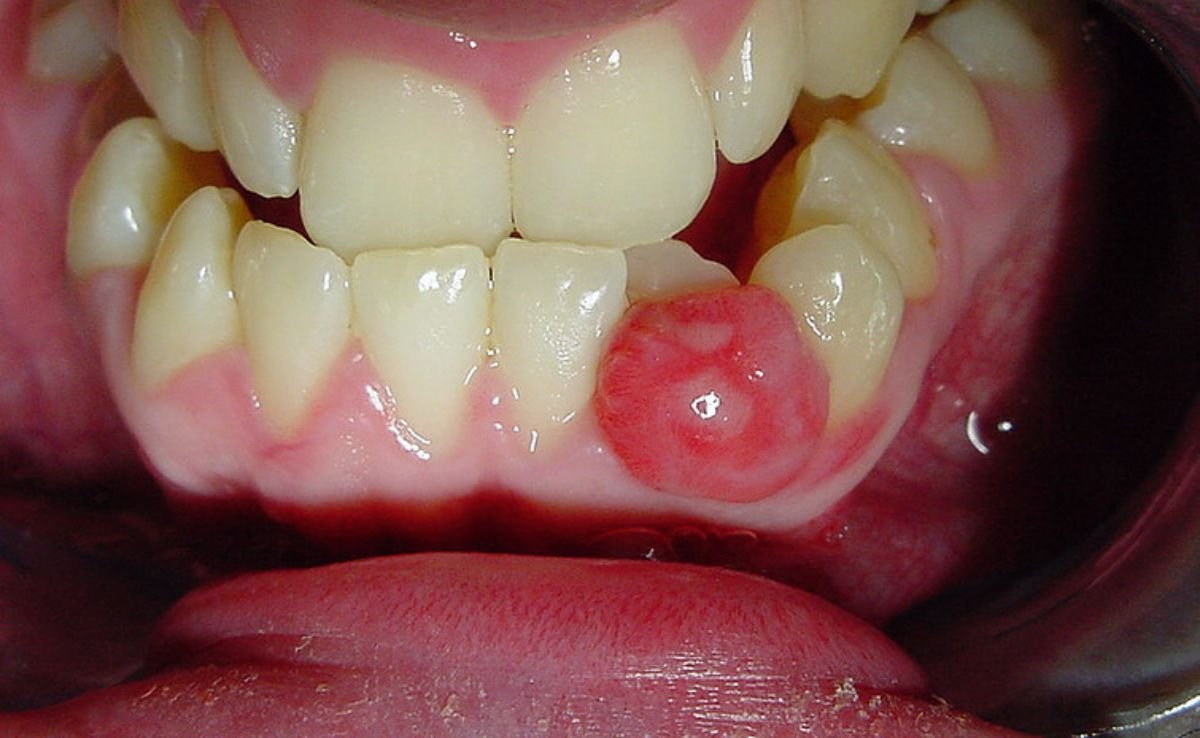

Oral and maxillofacial surgery may be necessary when your condition involves more than just the teeth, particularly the jaw, facial structure, or surrounding soft tissues. Some common situations where this surgery might be recommended include:

This type of surgery is often the bridge between general dental care and more advanced solutions, especially when structural or functional correction is involved.